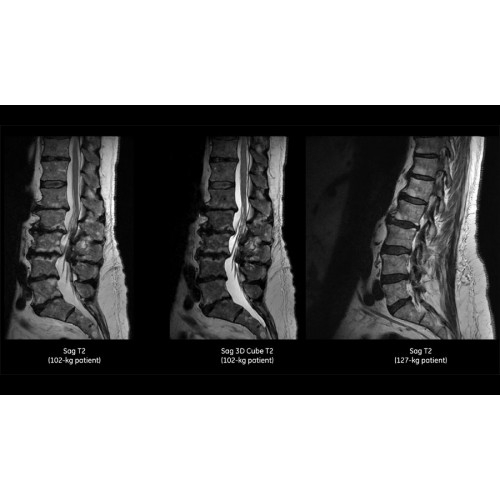

• Технология Digital Surround Technology (DST) — это новая технология объемной оцифровки данных, объединяющая сигналы от каждого элемента катушки. Прекрасное соотношение сигнал/шум и чувствительность поверхностных катушек в сочетании с превосходной однородностью и высокой проникающей способностью встроенной радиочастотной катушки — все это позволяет создавать качественные изображения не только позвоночника, но и всего тела.

Благодаря революционному программному пакету Silent Suite уровень шума снижается до 77 дБ, что всего на 3 дБ выше уровня окружающей среды. Программный пакет Silent Suite теперь включает полный пакет приложений для исследования ЦНС (T1, T2 FLAIR, DWI10, МРА). Кроме того, мы расширили возможности визуализации Silent за пределы ЦНС для исследований скелетно-мышечной системы и позвоночника. Silent Suite – платформа, содержащая в себе все импульсные последовательности для бесшумного сканирования.